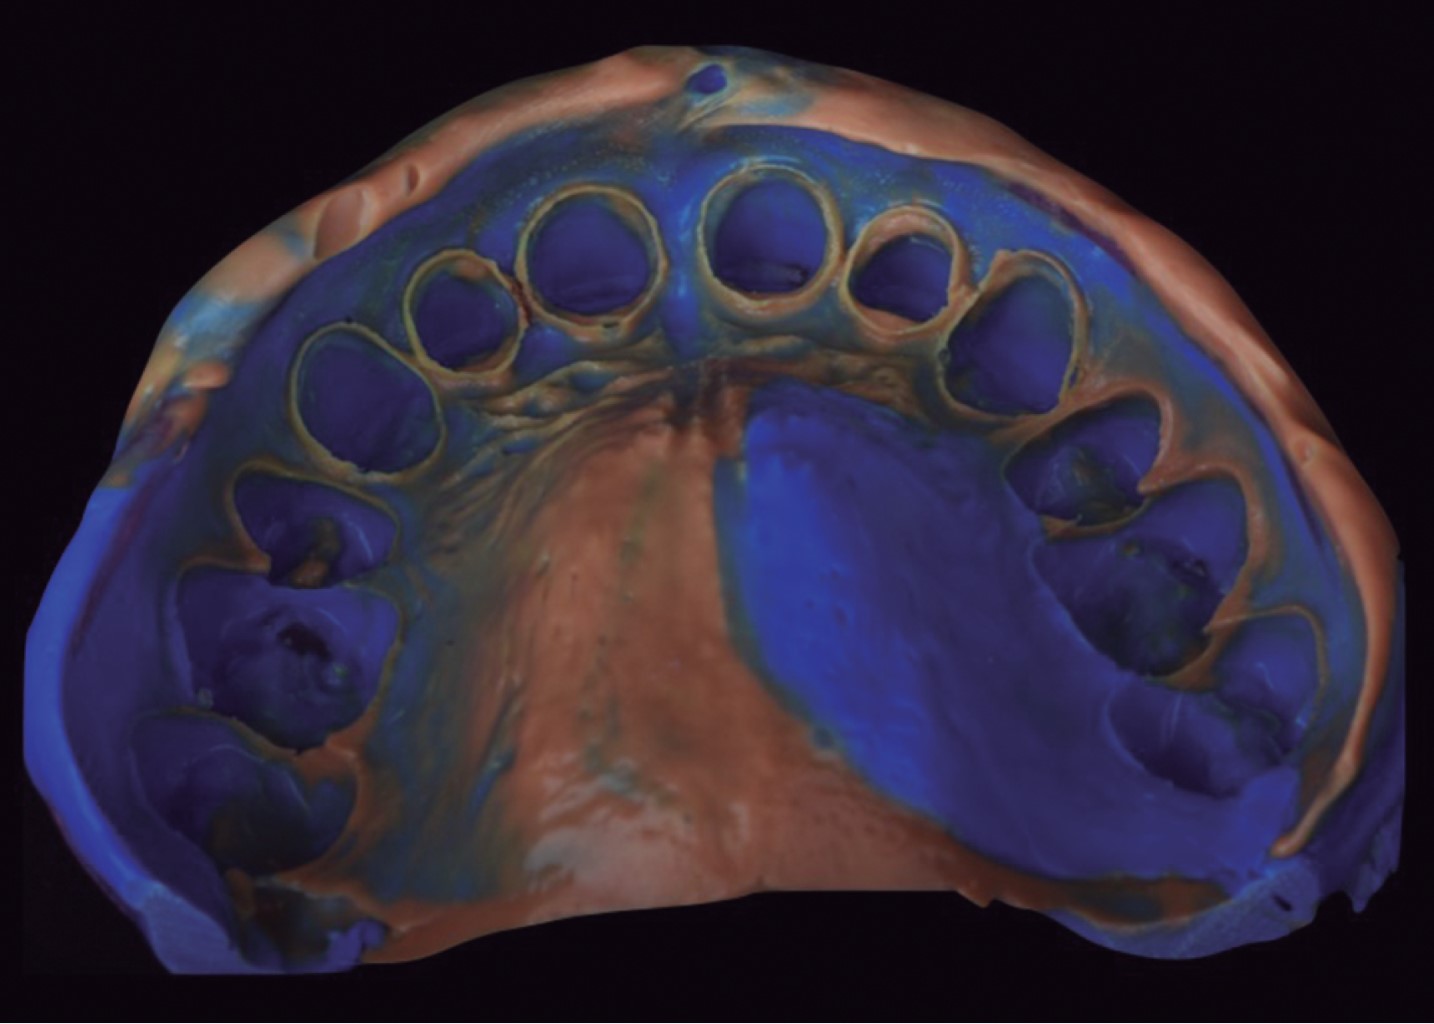

Para la toma de impresión definitiva se realizó una cucharilla individual con Palatray (Kulzer) con polivinilsiloxano (Express, 3M) con técnica de un hilo (000, Ultradent) (Figura 6). Posteriormente se tomaron registros de mordida Pattern Resin (GC) al igual que arco facial para montar los nuevos modelos en articulador semiajustable (PCH-Panadent) y se realizaron los provisionales de acrílico con la misma guía de silicón.